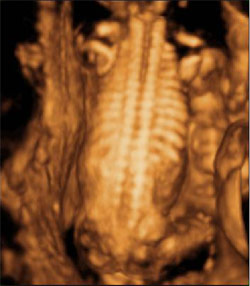

Ecografía 3D de la columna y costillas de un feto en el tercer trimestre de embarazo

En la imagen ecográfica se puede apreciar con claridad la columna vertebral y las costillas del feto. En determinadas ocasiones, la ecografía en tres dimensiones ayuda a precisar ciertos diagnósticos de anomalías fetales.